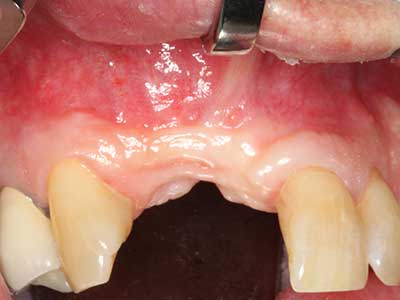

Marginale Parondontalerkrankungen stellen im fortgeschrittenen Alter den Hauptgrund für Extraktionen dar. Sie basieren im Wesentlichen auf einer bakteriellen Besiedlung der Zahnfleischtasche und hierdurch bedingten Entzündung mit konsekutivem Verlust des Zahnhalteapparates. Die Ausbildung subgingivaler Biofilme und Konkremente stellt einen wesentlichen ätiologischen Faktor für den marginalen Knochenabbau dar, so dass ihrer Entfernung eine wesentliche Bedeutung in der Therapie zukommt (Drisko 2014, Plessas 2014).

Zur Behandlung einer marginalen Parodontitis lassen sich eine initiale und chirurgische Therapiephase unterscheiden. Neben der Mundhygieneinstruktion und -motivation sollte in beiden Phasen eine suffiziente Reinigung der Wurzeloberfläche erfolgen, wobei im regenerativen Setting zumeist ein offener Zugang gewählt wird. Die Reinigung der Wurzeloberfläche kann durch die Verwendung spezieller Ansätze auch piezochirurgisch erfolgen, wobei unterschiedlich gebogene Instrumente auch schlecht zugängliche Bereiche wie Furkationen erreichen. Die systemimmanente Wasserkühlung spült dabei die gelösten Konkremente und Bakterien aus der Tasche. Um zusätzlich die Abtragung von Zahnhartsubstanz zu minimieren, wurde bei speziellen Systemen wie dem Piezomed ein Applikations-Feedback eingebaut. Hierbei wird die Abtragungsleistung konsequent reduziert, je mehr Druck auf den Parodontalansatz ausgeübt wird.